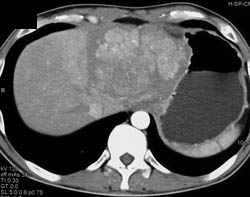

Hepatoma